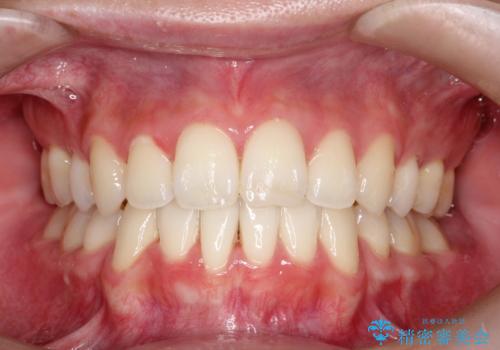

抜歯矯正により、前歯をしっかり下げることで口元がすっきりしました。